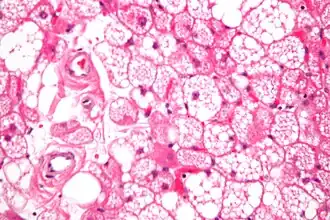

L'hibernome est une tumeur bénigne développée aux dépens de la graisse brune.

On distingue quatre types histologiques d'hibernome : typique, myxoïde, lipome-like et à cellules fusiformes[1],[2].